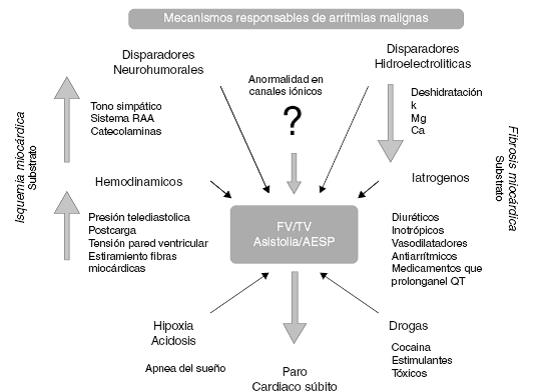

Para que se presente un episodio de FV o TV se requiere la participación de sustratos y disparadores de arritmias como se muestra en la Figura 1. Los sustratos más importantes son la isquemia, la fibrosis miocárdica4,8,13,14 y las anomalías genéticas13,30. La isquemia miocárdica favorecerá la dispersión de los períodos refractarios a nivel de las células del miocardio ventricular4,8, la fibrosis miocárdica favorece el desarrollo de circuitos de reentrada ventricular14,15 y las anomalías genéticas en los canales iónicos favorecen alteraciones en la despolarización o repolarización ventricular13. Varios disparadores de arritmias están involucrados, entre los que podemos encontrar: 1) Incremento en la actividad del sistema nervioso autónomo, en la actividad neurohumoral, del sistema renina angiotensina e incremento en el nivel de catecolaminas circulantes; 2) Factores hemodinámicos como aumento de presión telediastólica, de la poscarga, de tensión de la pared ventricular y estiramiento de las fibras de miocardio ventricular; 3) Alteraciones hidroelectrolíticas como hiponatremia, hipocalemia, hipocalcemia, hipomagnesemia y deshidratación; 4) Hipoxia; 5) Acidosis; 6) Factores iatrogénicos secundarios al uso de fármacos como diuréticos, inotrópicos, vasodilatadores, antiarrítmicos o fármacos que prolongan el intervalo QT o que favorecen patrones electrocardiográficos tipo Brugada; 7) Alcohol y drogas como cocaína o LSD y 8) Estimulantes como metilfenidato, exceso de cafeína, exceso de ejercicio, etc. 4,8.